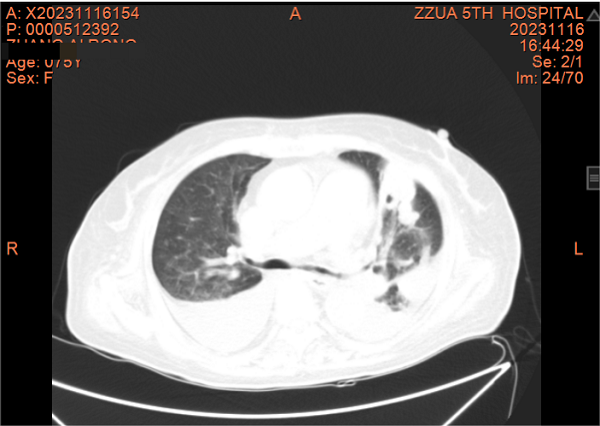

张阿姨既往患“冠心病、不稳定型心绞痛、持续性房颤、慢性心衰、肺动脉高压、高血压、2型糖尿病、下肢静脉血栓”等多种疾病,一直未规范慢性病管理,血糖控制也较差,1年前感染新型冠状病毒后出现间断胸闷心悸并反复双下肢水肿,间断服用利尿剂治疗,效果不好。张阿姨求诊郑州市某医院治疗,考虑新冠病毒感染并发念珠菌肺炎、念珠菌尿路感染,因尿潴留留置导尿管导尿,经抗病毒、抗真菌等治疗后好转出院,院外继续服用抗真菌及纠正心衰药物。出院2天后自行拔除导尿管,出现不能排尿及腹胀、嗜睡、乏力、气喘、不能行走、双下肢凹陷性水肿症状,痛苦中的张阿姨求诊至郑州大学五附院全科医学科。

接诊医师别柏林检查病人后考虑为急性尿潴留并多病共存患者,病情危重,夏雪娇护士长及护理团队立即给予留置导尿管导尿、吸氧、心电监护并加强护理,入院化验提示合并甲型流感病毒感染,医疗组积极给予抗真菌、抗流感病毒、抗细菌、消肿、减轻心脏负荷、抗凝、控制心率及补充蛋白等综合治疗,患者一体多病,慢病管理较差,别柏林医师对张阿姨加强慢性病管理及用药指导。经悉心治疗后,张阿姨逐渐可以下床活动了。

此外,张阿姨一直迫切希望能够尽量恢复正常排尿,拔除尿管,正常生活。患者经会诊及检查考虑神经源性膀胱可能性大,夏雪娇护士长看在眼里急在心里,指导家属给予规范腹部按摩,叮嘱患者主动下床排尿锻炼,经护患协作,张阿姨自主排尿功能很快恢复,了却了张阿姨的心愿。免疫力下降,一体多病的张阿姨住院期间又出现左侧胸壁多发皮疹、水疱,考虑为带状疱疹,经抗病毒及对症治疗,同时护理团队加强破损皮肤管理,张阿姨的带状疱疹很快痊愈出院。出院后张阿姨按照医嘱随诊、服药,日常生活能够自理,慢性病得到较好管理,念珠菌肺炎逐渐好转。

一个月前,张阿姨再发胸闷、心悸,这次张阿姨主动找到了全科医学科。住院期间因受凉出现鼻塞、流涕、发热,病情进展迅速,咳嗽、咳痰、胸闷、心悸、气喘等症状明显加重,动脉血气提示Ⅰ型呼吸衰竭并代谢性酸中毒。张阿姨精神特别差,情绪也十分低落。全科医学科主任刘培杰主任医师及别柏林主治医师综合分析病情后,第一时间给予碳青霉烯类积极抗感染、糖皮质激素抗炎、硝酸酯类扩张血管减轻心脏负荷、控制快速心室率、经鼻高流量湿化氧疗等综合治疗,护理团队给予饮食指导及心理辅导,张阿姨的病情很快得到控制,经复查胸部CT,肺部病变较前明显吸收,出院时再次对其慢性病管理及预防、治疗措施对其进行了再次的细致交代,病情好转出院。